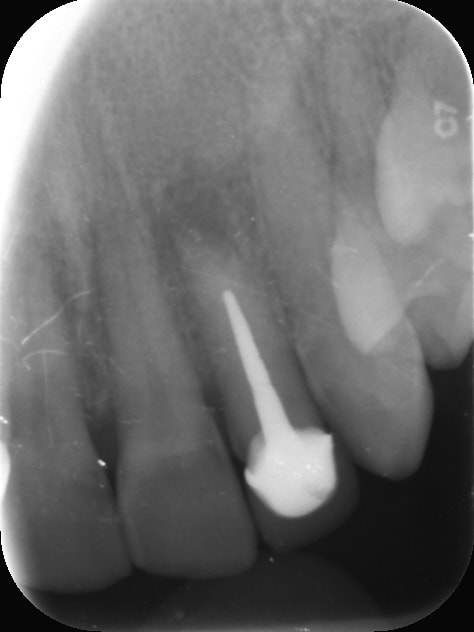

C'est la pulpe, c'est la pulpe !

Pulpe rétractée on va s'amuser à travers le bridge. -)

Capture d écran 2017 02 09 15.32 - Eugenol

Oh! C'est tout droit, tu nous as montré plus difficile.

Tout tout droit, une fois que tu es dedans oui :)

Avant d'être au chaud, il y a moyen de faire des bêtises :)

Je préfère faire celle là tu vois.

Capture d écran 2017 02 09 15.06 - Eugenol

il n'y a pas photo. Allez je te fais confiance, plein de RX pour valider ton axe et ton approche et tout va bien se passer. Avec un peu de chance tu flingueras le bridge et il sera à refaire ;-)

Piliers 34 et 38 faut oser. -)